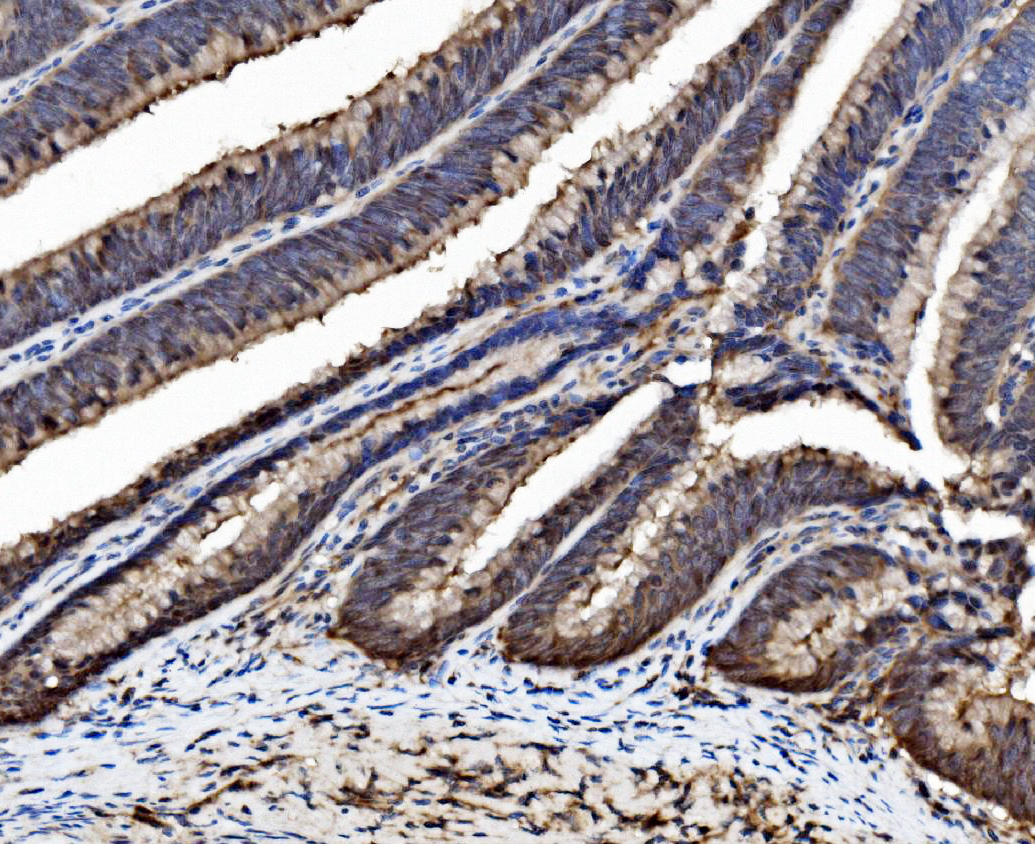

IHC analysis of Caspase 6/CASP6 (large) using anti-Caspase 6/CASP6 (large) antibody (BA3969).

Caspase 6/CASP6 (large) was detected in a paraffin-embedded section of human Colorectal adenocarcinoma tissue. Biotinylated goat anti-rabbit IgG was used as secondary antibody. The tissue section was incubated with rabbit anti-Caspase 6/CASP6 (large) Antibody (BA3969) at a dilution of 1:200 and developed using Strepavidin-Biotin-Complex (SABC) (Catalog # SA1022) with DAB (Catalog # AR1027) as the chromogen.